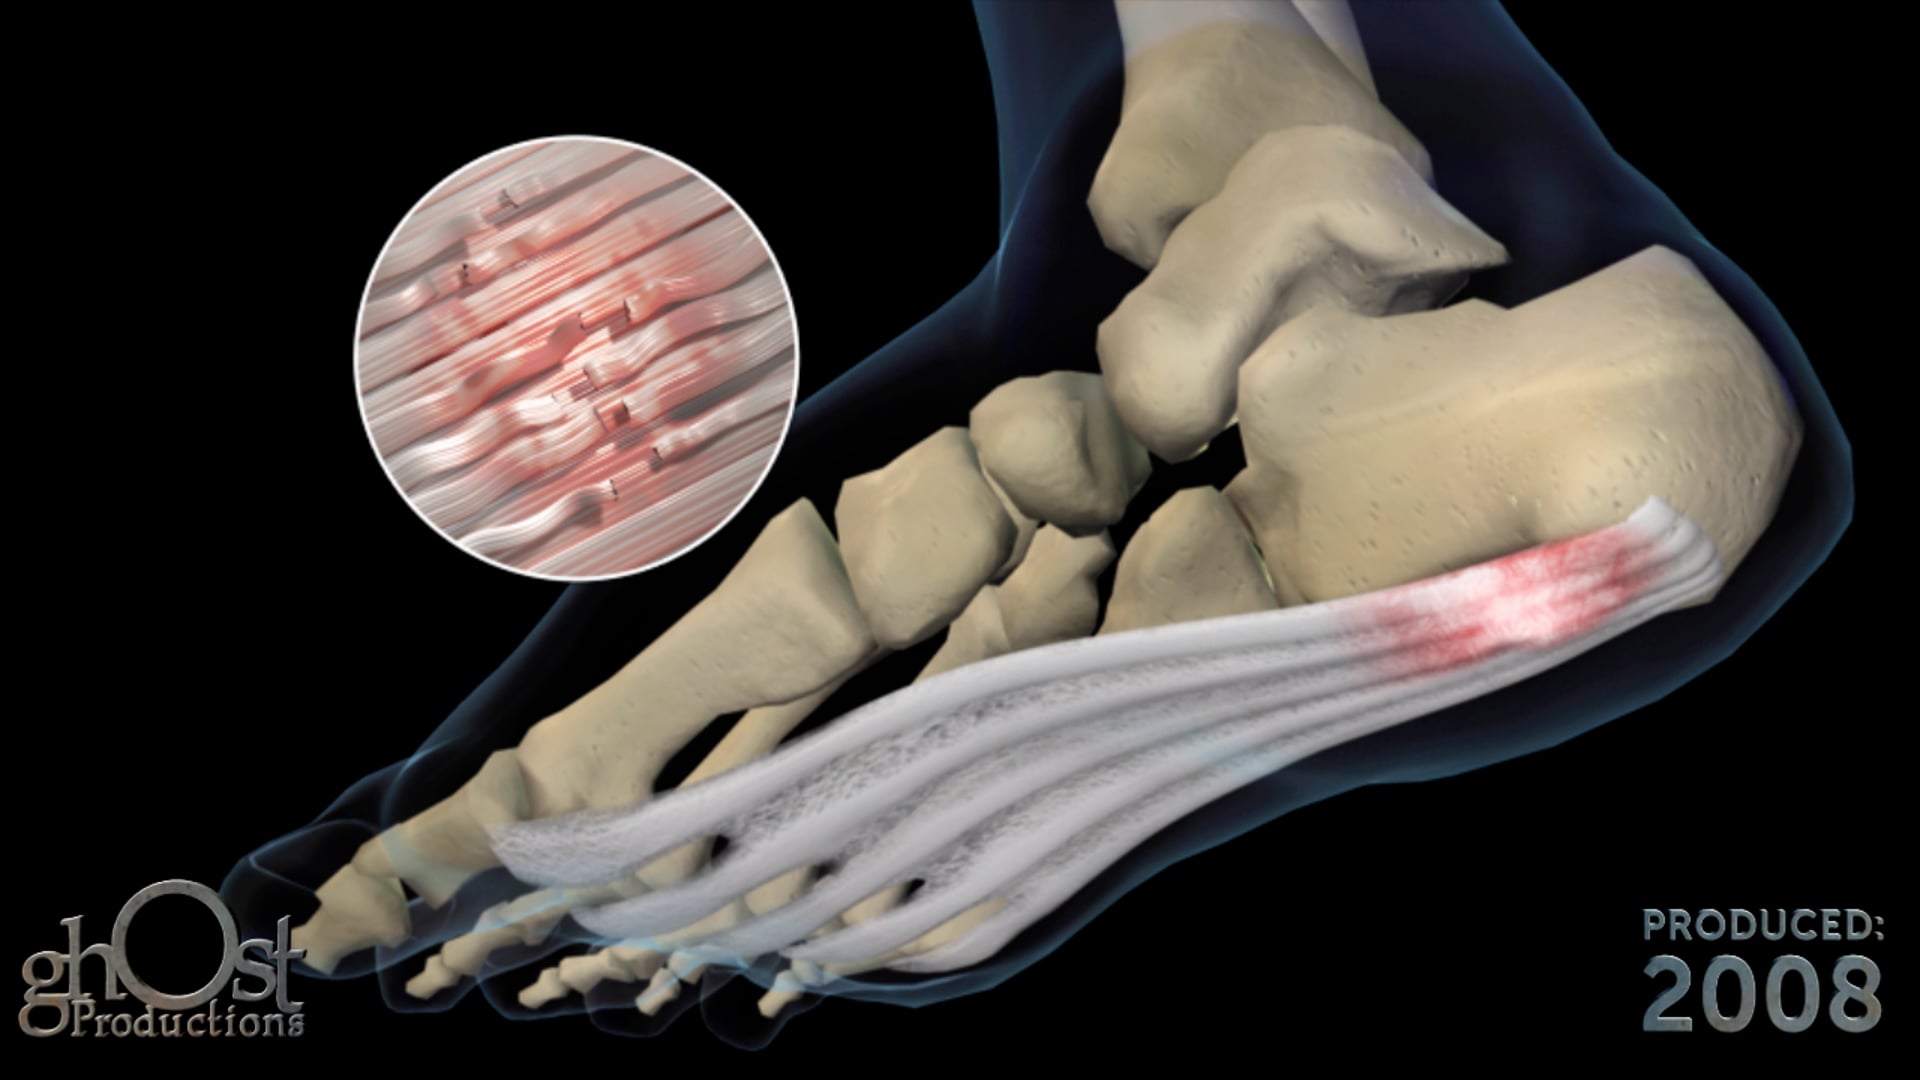

Ghost Productions, a leading medical animation company, created a stunning animation to showcase their talents at the 2009 American Association of Orthopedic Surgeons (AAOS) in Las Vegas. The animation features a character who suffers from multiple bone fractures and undergoes surgical repairs in under 3 minutes. The video highlights various orthopedic surgeries, including clavicle, shoulder, wrist, fibula, tibia, knee, femur, hip, spine, and hand surgeries. The animation is medically accurate and showcases Ghost Productions' expertise in the field of orthopedic surgery. This video is a testament to the company's commitment to creating high-quality medical animations that educate and inform healthcare professionals and patients alike.

Ghost Productions built this medical animation from the ground up to showcase the talents of Ghost Productions at the 2009 American Association of Orthopedic Surgeons (AAOS) in Las Vegas. Instead of showing pre-existing client work in our reel, we thought it would be more fun to make a character animation, break nearly every bone in his body, and then surgically repair him in under 3 minutes.